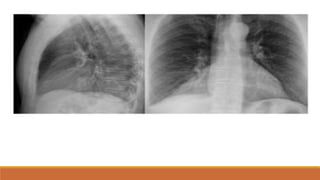

TDMP TỰ DO

PHIM THẲNG ĐỨNG

•TÙ GÓC SƯỜN HOÀNH

•BÓNG MỜ VÙNG THẤP XÓA BỜ VÒM HOÀNH VỚI

GIỚI HẠN TRÊN LÀ ĐƯỜNG CONG DAMOISEAU

•ĐẨY TRUNG THẤT VỀ PHÍA ĐỐIDIỆN

•XẸP PHỔI THỤ ĐỘNG (+/-)

•THAY ĐỔI THEO TƯ THẾ

PHIM NGHIÊNG

•TÙ GÓC SƯỜN HOÀNH TRƯỚC VÀ SAU

•BÓNG MỜ VÙNG THẤP VỚI GIỚI HẠN TRÊN LÀ

ĐƯỜNG CONG LÕM XUỐNG DƯỚI